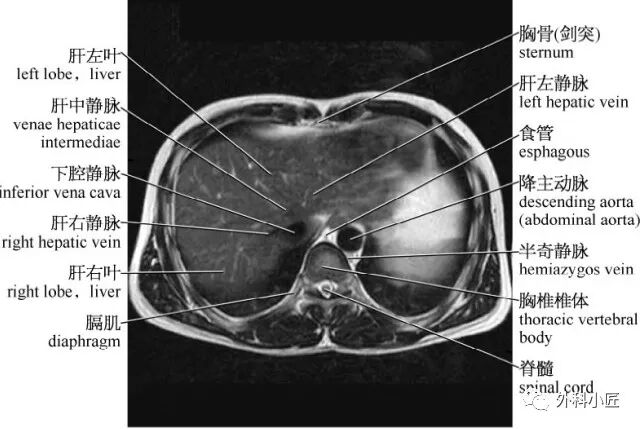

腹部影像学解剖图谱拿走不谢

图片尺寸1072x712